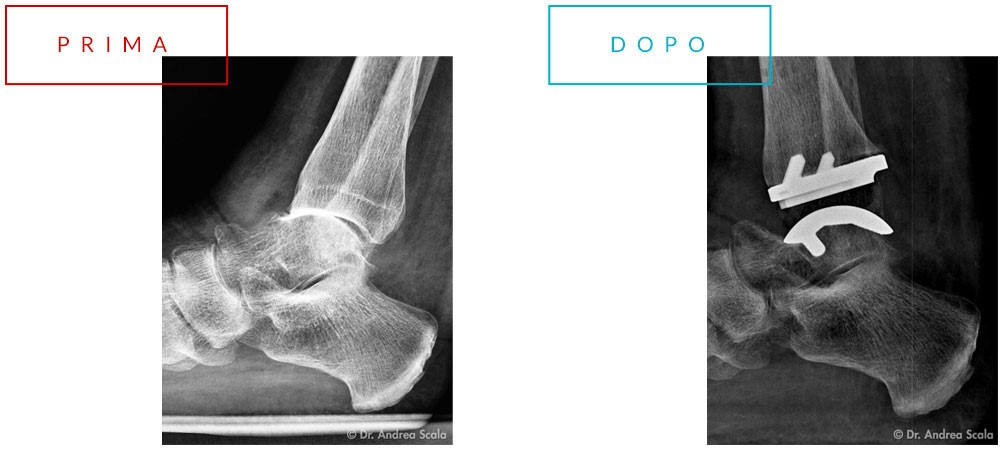

Cos’è la protesi totale della caviglia?

La protesi totale della caviglia è una procedura chirurgica eseguita da chirurghi ortopedici specializzati nel piede e nella caviglia per il trattamento delle gravi forme di artrosi.

La protesi consiste nel rimuovere la superficie artrosica dell’estremità della tibia e dell’astragalo (osso del piede) e rivestirle con componenti metalliche. Le componenti metalliche vengono separate da una componente di plastica molto resistente (polietilene). L’operazione è del tutto analoga alla protesi d’anca e alla protesi di ginocchio.

La Protesi totale della caviglia

Con questa procedura, il movimento viene ripristinato e il dolore viene eliminato.

Questo riduce lo stress sulle articolazioni del piede che sono accanto alla caviglia. Viene così diminuita la possibilità di sviluppare l’artrosi. I nuovi disegni di impianti hanno percentuali di successo molto migliori rispetto ai disegni più vecchi. La capacità della nuova articolazione della caviglia di muoversi su e giù è considerata il vero vantaggio rispetto alla fusione della caviglia. Salire e scendere normalmente le scale non potrà mai accadere con l’artrodesi della caviglia!